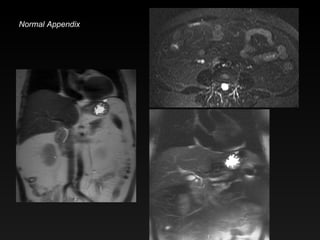

Normal appendix

MR Appendicitis Dilated fluid-filled appendix Peri-appendiceal edema Thickened wall Enhancement (if Gd is given)